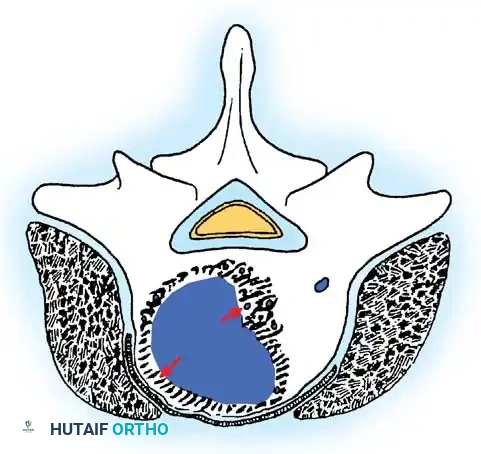

Stage 2: Active Tumors

Stage 2 tumors (e.g., osteoid osteoma, standard osteoblastoma, aneurysmal bone cysts) grow slowly and cause symptoms, usually pain or deformity. They possess a reactive pseudocapsule. Treatment usually involves en bloc excision where anatomically feasible, though meticulous intralesional excision combined with local adjuvants (liquid nitrogen, phenol, or polymethylmethacrylate [PMMA]) often suffices.

Cross-sectional representation demonstrating the expansion of an active Stage 2 benign lesion within the vertebral body, respecting the outer cortical margins but requiring meticulous intralesional clearance.